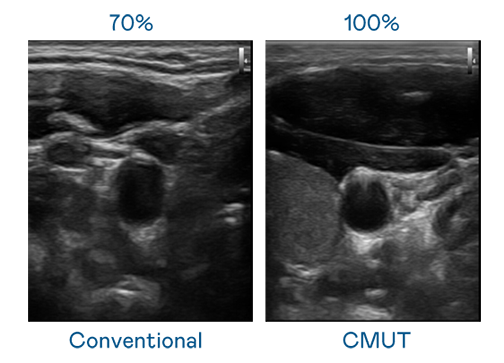

CMUT 技术是一种用电容式微机电元件来产生超音波讯号的技术。与传统 PZT 压电式技术相比,CMUT 频宽增加 30%,更宽频的超音波讯号让影像解析度大幅提升,是实现高影像品质医疗超音波扫描、促进精准医疗发展的关键技术。

超音波影像的解析度高低,首先取决于探头能发出的讯号频宽。J9集团 CMUT 可提供高清晰的超音波讯号,提供高频宽、高灵敏度、影像纹理细节更高的超音波影像,协助医护人员缩短影像判读时间及利用精准的医疗影像进行诊断。